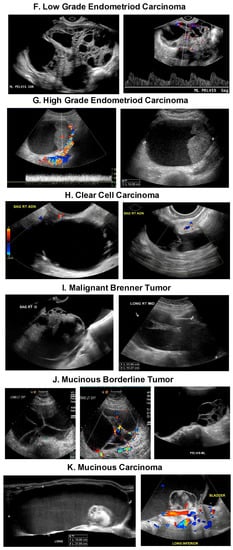

5. Ovarian Mass Ultrasound Morphology

| Type/Precursor | -Endometrioid carcinoma/Endometriosis -Clear cell carcinoma/Endometriosis Mucinous carcinoma/Mucinous Cystadenoma, Endometriosis, Teratoma, -Brenner Tumor, and Mucinous borderline tumor -Low grade serous carcinoma/Serous cystadenoma, Adenofibroma, Atypical proliferative serous tumor, Mullerian epithelial cyst -Transitional cell carcinoma or Malignant Brenner tumor/Brenner tumor | -High grade serous carcinoma/Probably de novo starting at the tubo, ovarian surface epithelium, serous tubal intraepithelial carcinomas (STIC) or ovarian hilum stem cell -Undifferentiated carcinoma? -Malignant mixed carcinoma? |